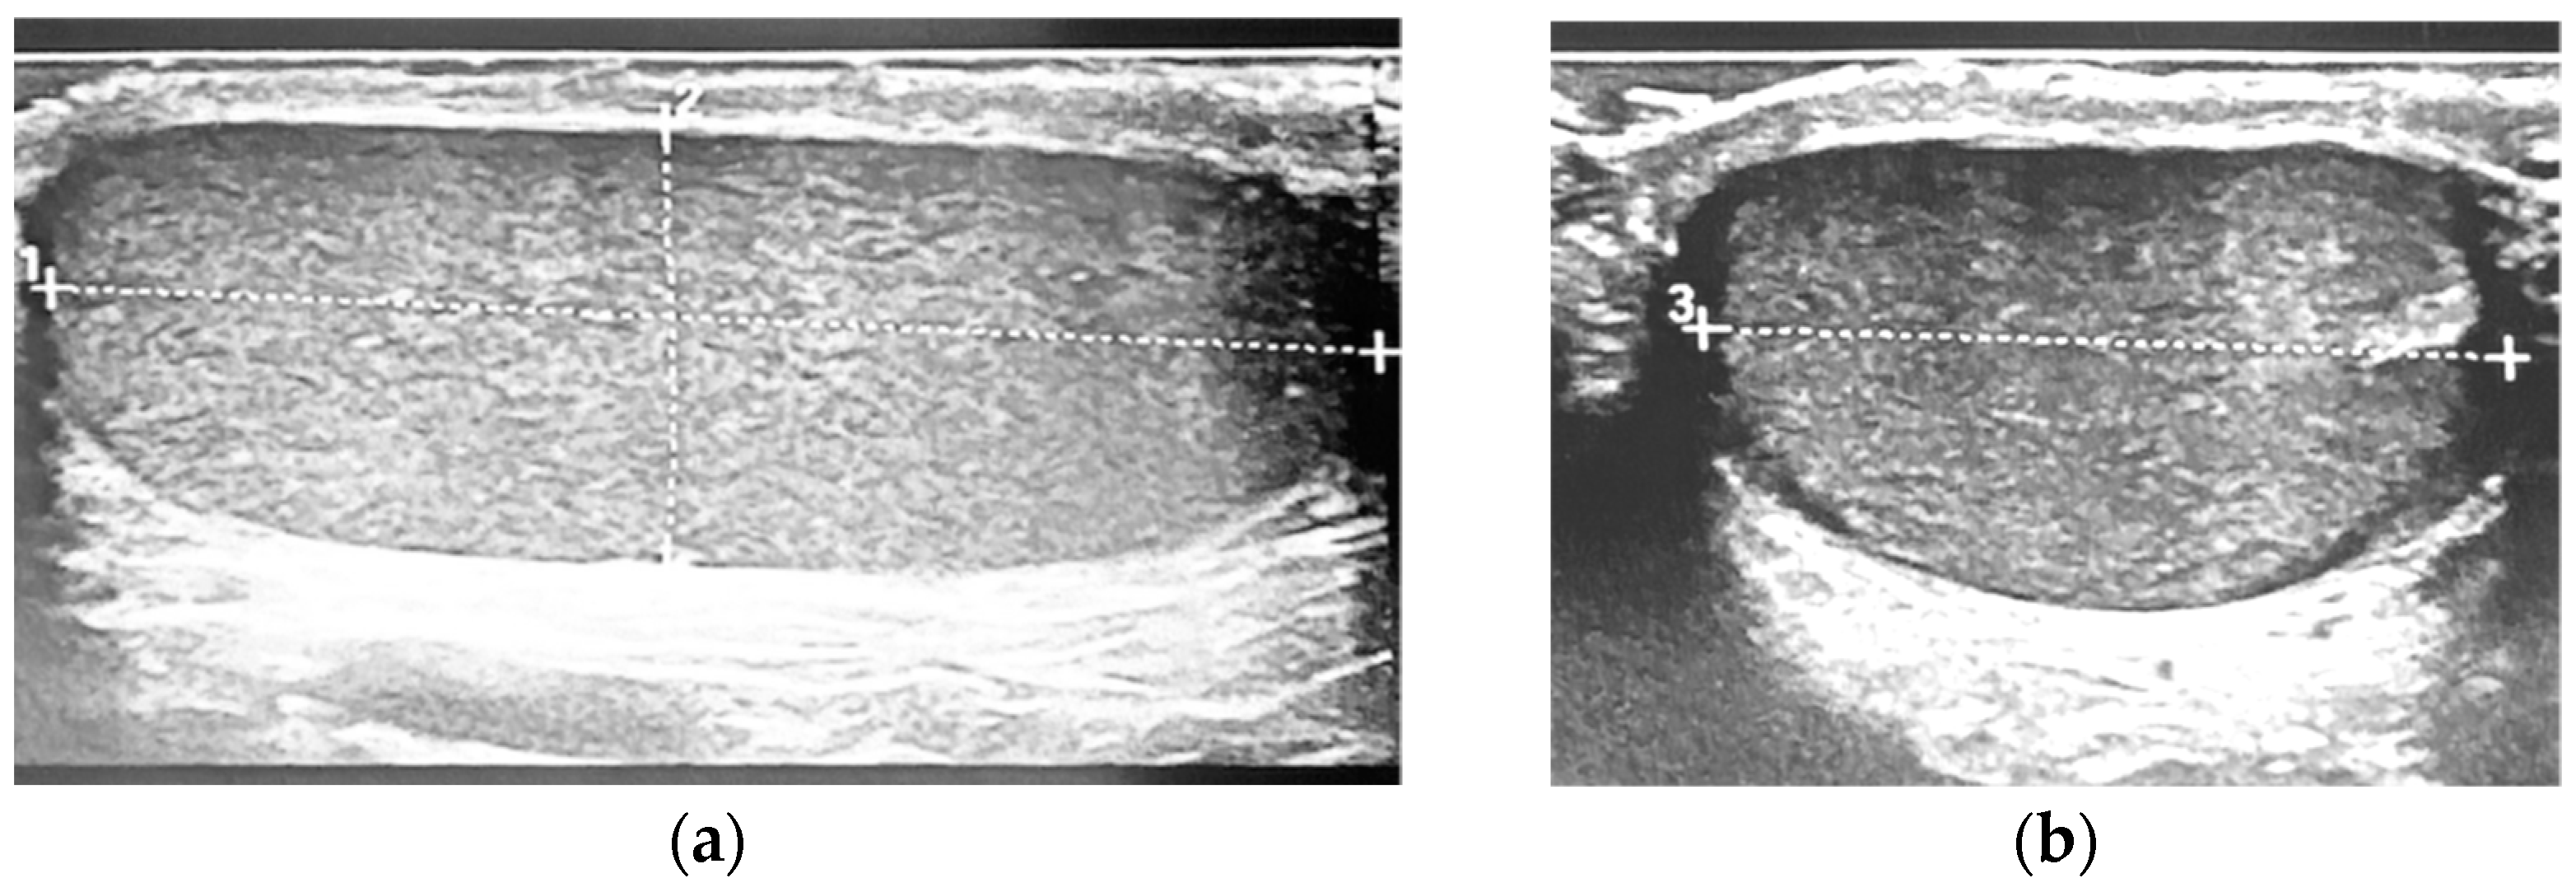

The probands were in prone position with slightly spread legs. No scrotal pad was used to support the testicles. Measurements of both testicles were performed using a copious amount of warmed coupling gel in two standardized directions to allow for optimal accuracy: A longitudinal measurement with slight angulations in both directions was carried out first to determine the largest longitudinal diameter (L). In this setting, the height (H) of the testicle was also measured at its widest point. The second measurement was then carried out in an axis perpendicular to the first measurement to determine the width (W) of the testicle (Figure 1).

Figure 1. Example of the standardized ultrasound technique used: (a) length (dotted line 1) and depth (dotted line 2) measured on the sagittal view; (b) the probe is then placed per-pendicular and the widthwidth (dotted line 3) is obtained at the broadest point.